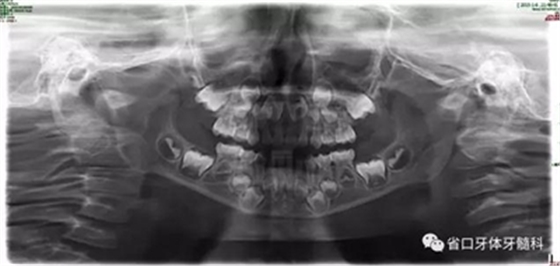

圖9 全景片